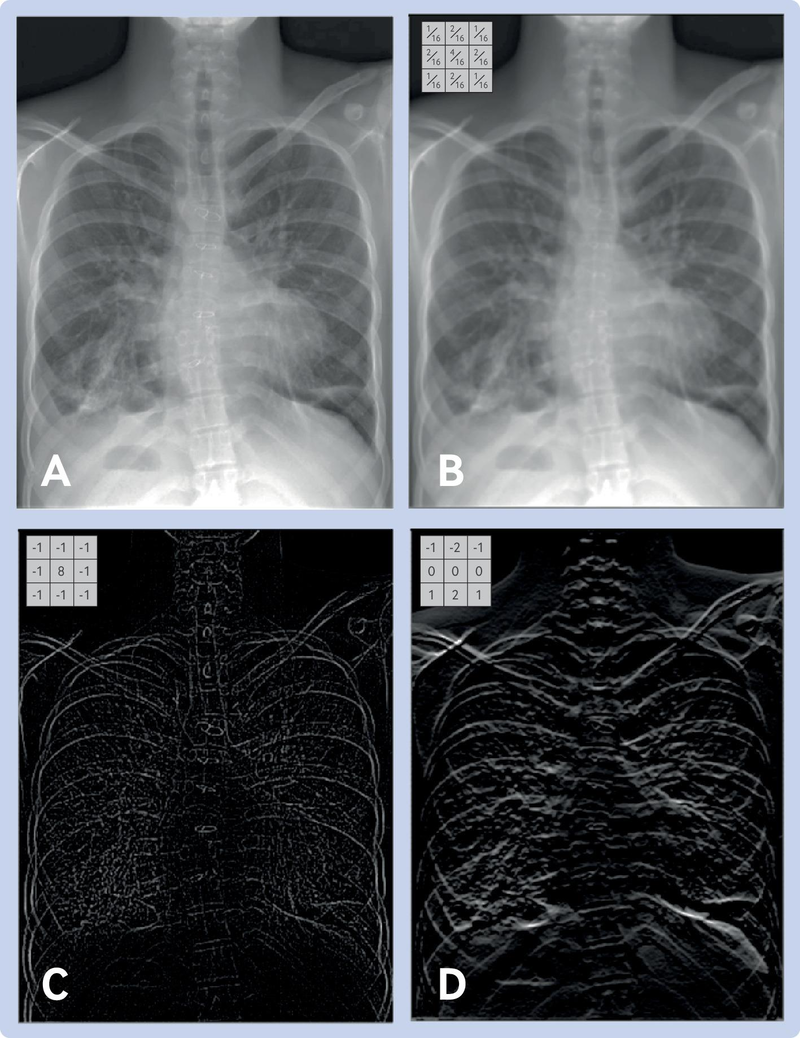

![]()

-

Grayscale: Single intensity value per pixel (0–255 for 8-bit). 0 = black, 255 = white. Used in many medical images (X-rays, CT scans).

RGB: Three values per pixel (Red, Green, Blue), each 0–255. Shape in memory: (height, width, 3) for NumPy, (3, height, width) for PyTorch.

CNNs use small learned filters (e.g., 3×3) that slide across the image, sharing parameters at every position. This avoids the parameter explosion of fully connected layers and preserves spatial structure. Stacking convolutional layers builds a hierarchy of features — edges → textures → parts → objects: